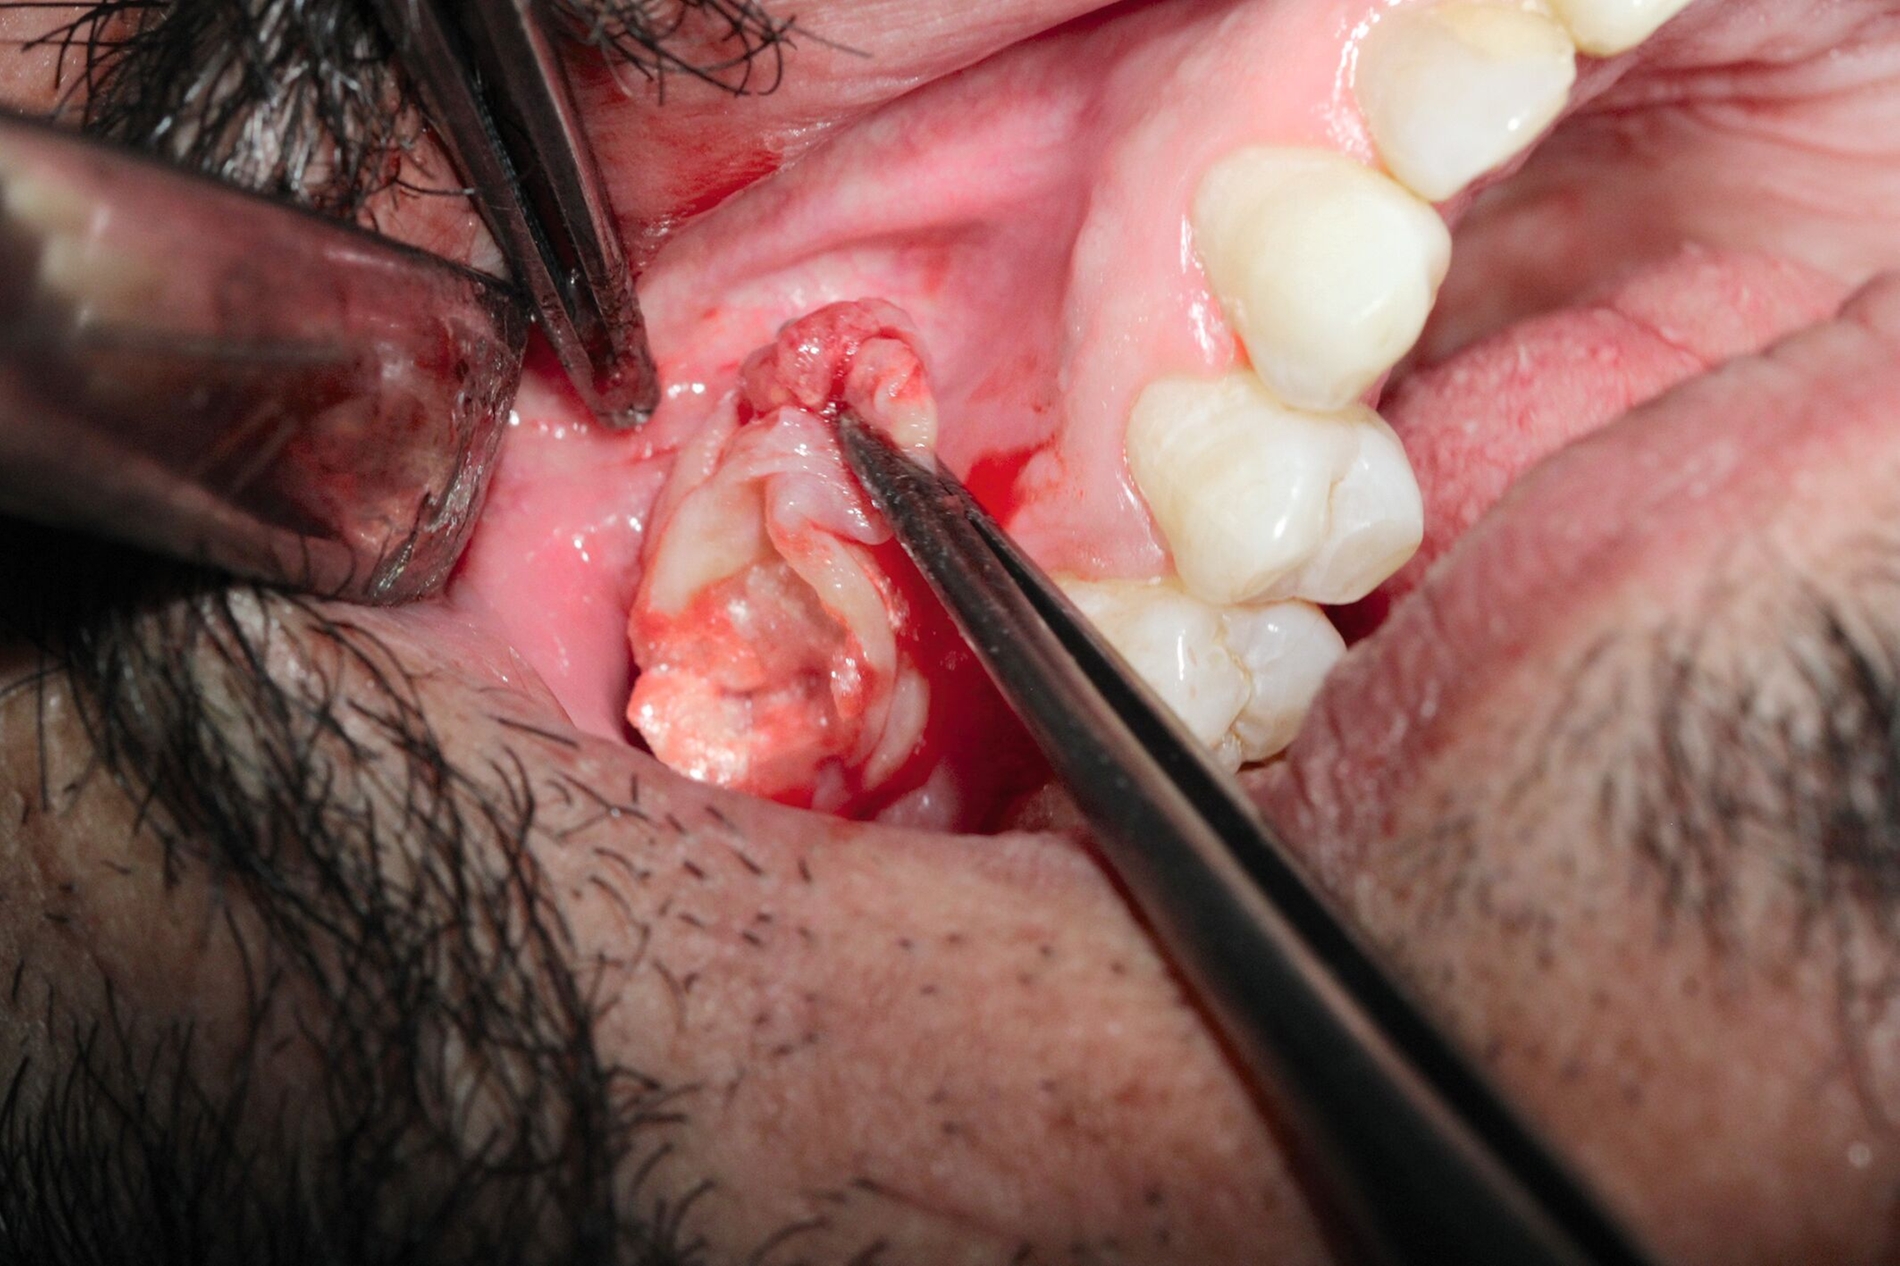

Die Zahnextraktion der Zähne 17 und 18 verlief komplikationslos. Drei Wochen später stellte sich der Patient zur Wurzelspitzenresektion an Zahn 24 vor. Nach schriftlicher Genehmigung des Patienten erfolgte eine Zystektomie in beiden Kieferhöhlen (Abbildungen 3 und 4). Auf der linken Seite wurden die Wurzelspitzenresektion und die Zystektomie zur Vermeidung eines Kontakts zwischen der infizierten Wurzelspitze und dem Sinus maxillaris dabei über verschiedene Zugänge durchgeführt. Beidseits zeigte sich intraoperativ eine Epithel-bekleidete Zyste, die von der Kieferhöhlenschleimhaut beziehungsweise der Schneider‘schen Membran gut abgrenzbar und trennbar war – was für eine Schleimretentionszyste spricht. Bei der Entfernung entleerte sich eine muköse Flüssigkeit.